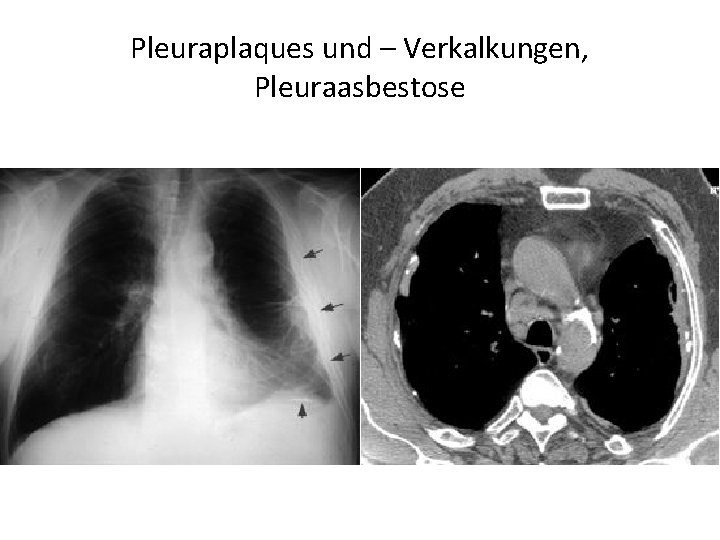

Pathologie der Pleurahöhle • Ein Pleuraerguss ist eine Flüssigkeitsansammlung im pleuralen Spaltraum • Ein Empyem ist eine Eiteransammlung im Pleuraspalt (wenn z. B. ein Lungenabszeß in den Pleuraspalt einbricht). • Pneumothorax: Wenn in den Pleuraspalt Luft tritt, hebt sich die Lunge von der Thoraxwand ab: es bildet sich der Pneuspalt eines Pneumothorax ("Pneu") aus. • Ein Hämatothorax ist eine Einblutung in den Pleuraspalt (z. B. bei Rippenfraktur). • Ein Chylothorax besteht bei Lymphe im Pleuraspalt. Die Lymphdrainage erfolgt über die viszerale Pleura. • pleuralen Tumoren • Pleuraplaques und –Verkalkungen, Pleuraasbestose

Pleuraplaques und – Verkalkungen, Pleuraasbestose